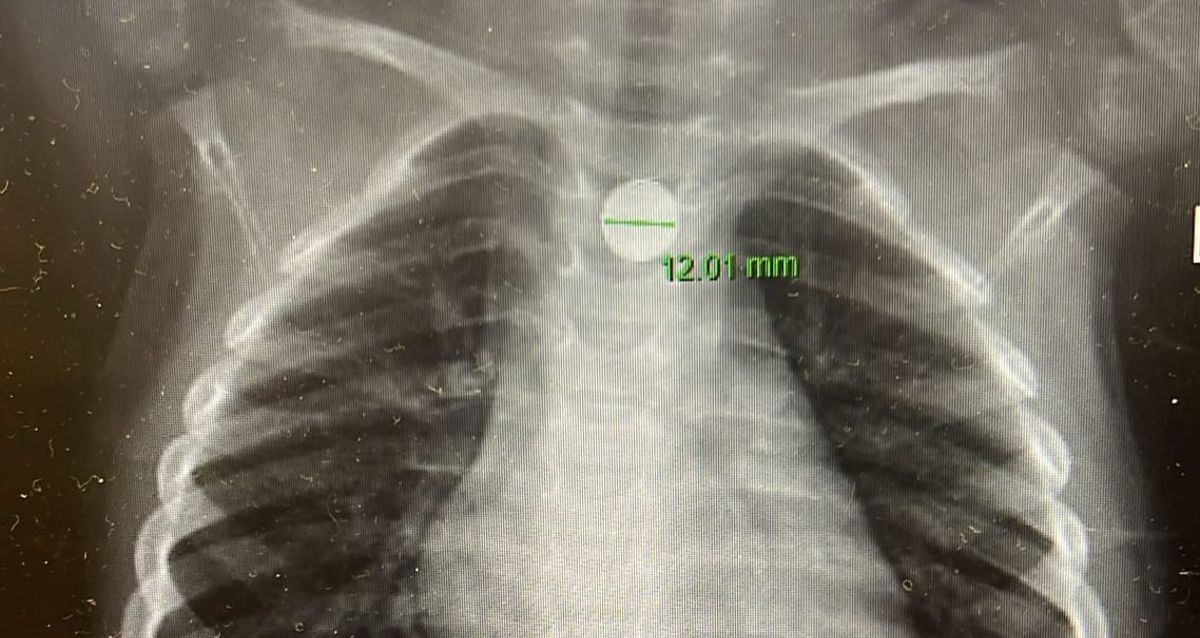

במלר”ד הילדים במרכז רפואי מאיר כפר סבא התקבל הילד על ידי ד״ר אהוד רוזנבלום, מנהל המלר”ד. צילום חזה שבוצע במקום זיהה סוללת דיסק התקועה בוושט – ממצא המחייב טיפול רפואי דחוף. בעקבות הממצאים הוזעק ד”ר אייל זיפמן, מנהל שירות גסטרואנטרולוגיה ילדים בבית החולים, והוחלט להכניס את הילד במהירות לחדר ניתוח.

“הסוללה נמצאה נעוצה בוושט ונשלפה בשלמותה באמצעות גסטרוסקופיה – פעולה אנדוסקופית שבה מוחדרת מצלמה דרך הפה לדרכי העיכול העליונות”, הסביר ד”ר זיפמן. “לאחר הוצאת הסוללה שטפנו את הוושט כדי להפחית את הפגיעה ההמשכית מהחומרים שמופרשים מהסוללה. למרות שחלף זמן קצר יחסית מרגע הבליעה, כבר נוצר כיב בוושט. לשמחתנו, בזכות התגובה המהירה של ההורים והטיפול המיידי, לא נגרם נזק משמעותי יותר”.